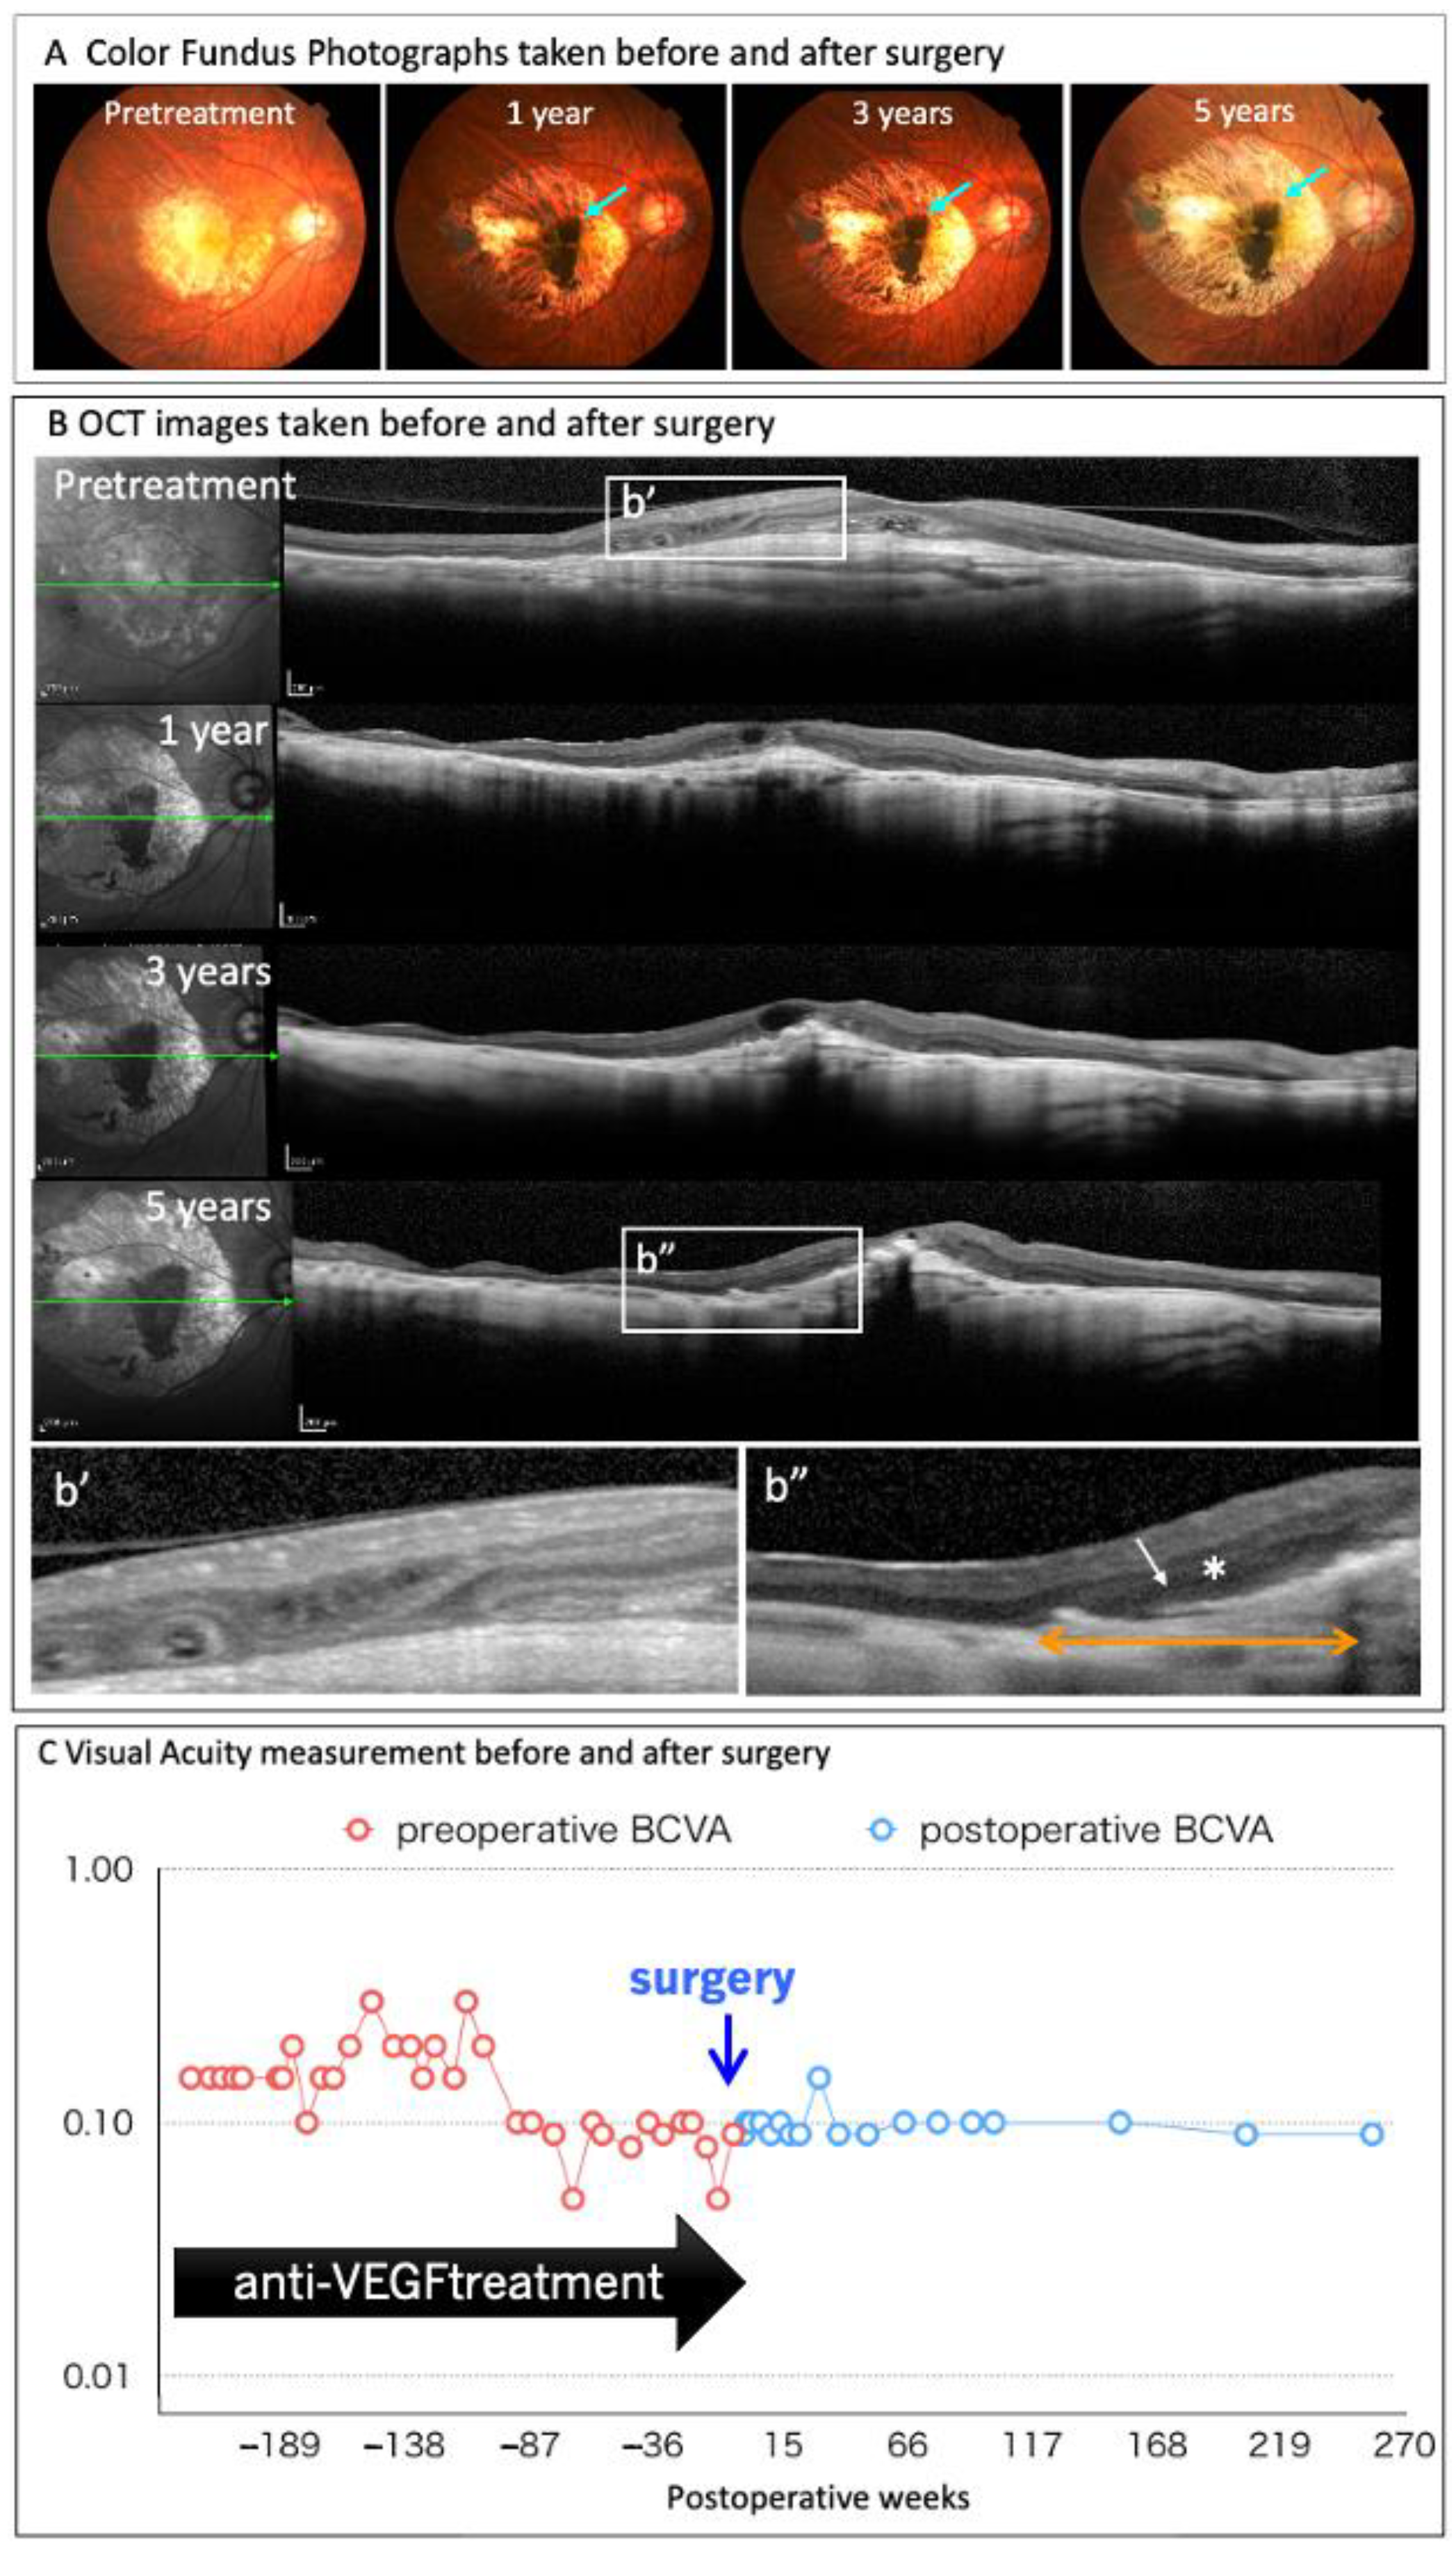

In August 2013, Takahashi launched a joint clinical research on autologous iPS cell-derived RPE cell sheet transplantation with RIKEN, Institute of Biomedical Research and Innovation Hospital, and Kobe City Medical Center General Hospital (UMIN000011929). Each subject’s skin was collected in November 2013, and CNV removal and RPE sheet transplant surgery were performed in September 2014. In September 2015, 12 months after the transplant surgery, safety and effectiveness were evaluated as the primary and secondary endpoints, respectively [6]. The four-year report has already been published [12], and the five-year follow-up has also been completed (Figure 2).

Figure 2.

Clinical findings of the autologous iPSC-derived RPE sheet transplanted to wet-type AMD patient at five years after surgery.

At five years after the surgery, the autologous iPSC-derived RPE sheet is stable the in sub-retinal transplantation site, while maintaining pigmentation. A slight increase in graft size is also noted (A, green arrows). Changes in the retinal structure before, and after, surgery are monitored using optical coherence tomography (OCT) (B). The ONL layer (*) and IS/OS line are identified at the RPE sheet-transplanted lesion (above the orange arrow), whereas the retinal structure is disrupted before surgery (b’). The patient’s corrected visual acuity is maintained after transplantation for five years without significant changes, and the anti-VEGF antibody treatment was completely discontinued after surgery (C).

None of the primary endpoints, including intraoperative complications, tumorigenesis, engraftment failure, rejection, or other severe complications of transplanted cells, were observed five years after surgery. Furthermore, CNV recurrence was not observed without additional anti-VEGF antibody treatment. The corrected visual acuity was maintained at 0.09, preoperatively. Regarding the graft, the area of the graft was 1.521 mm2 at three days after transplantation, increasing three-fold to 5.471 mm2 at one year after transplantation. The size of the RPE sheet was relatively stable three years after transplantation. The choroidal volume below the transplanted graft was relatively stable at five years after transplantation. Whereas, the volume of the choroid outside of the lesion covered with the graft decreased to 60% compared to the pre-transplantation volume. In addition, the National Eye Institute is conducting research to evaluate the safety and feasibility of subretinal transplantation using iPSC-derived RPE grown as a monolayer on a biodegradable poly lactic-co-glycolic acid scaffold, as a potential autologous cell-based therapy for GA preparations associated with AMD.